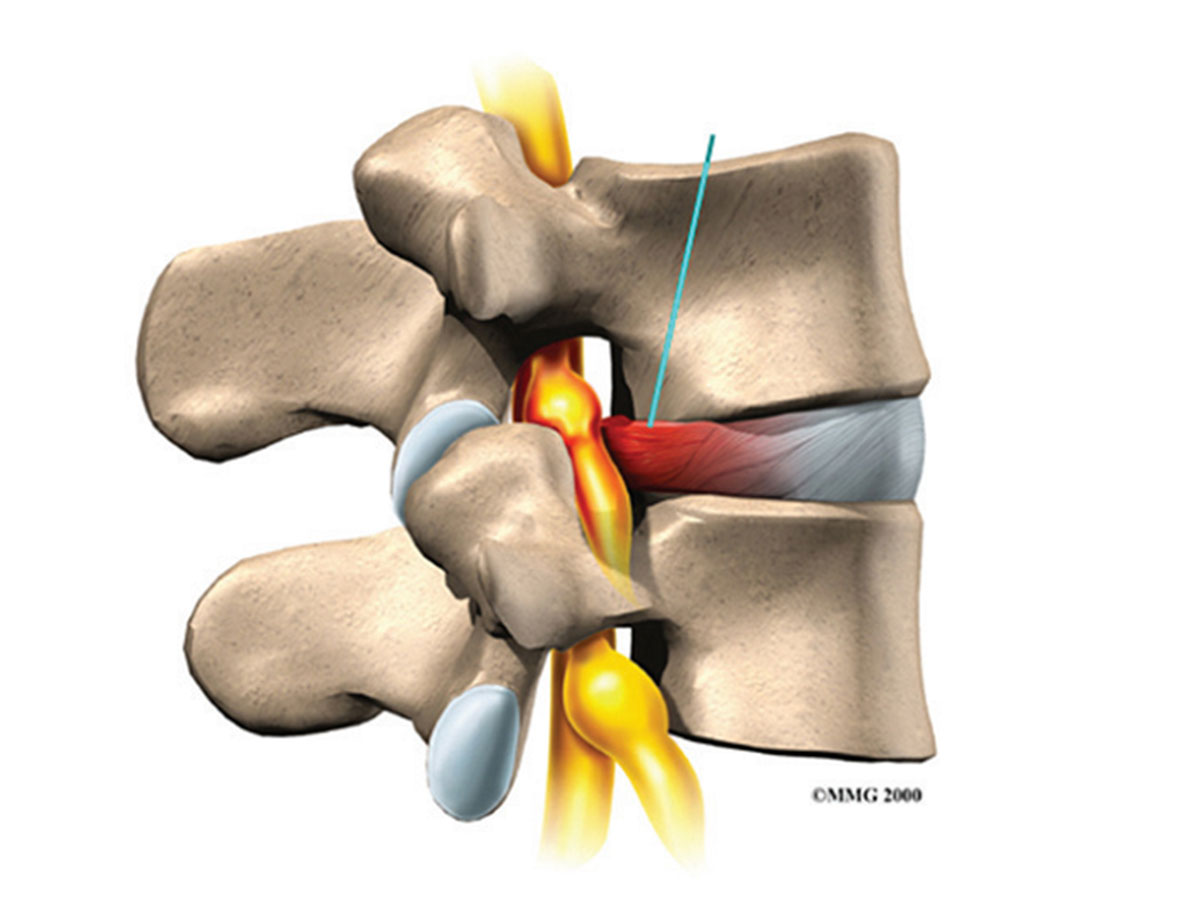

Lumens Disc Prolapse

A disc prolapsed is often referred to as a slipped disc, however please do not worry as your disc cannot “slip” anywhere. Think of your discs as shock absorbers between the vertebrae of your spine. What actually occurs, is the thick gel-like nucleus in the middle of the disc bulges out through a tiny fault in the fibrous disc wall. This small bulge of nucleus can therefore irritate and compress the nerve root causing pain, which may radiate down the leg. There are different types and severities of disc prolapse, which can be seen in the diagram below.

Cervical Disc Prolapse

A disc prolapsed is often referred to as a slipped disc, however please do not worry as your disc cannot “slip” anywhere. Think of your discs as shock absorbers between the vertebrae of your spine. What actually occurs, is the thick gel-like nucleus in the middle of the disc bulges out through a tiny fault in the fibrous disc wall. This small bulge of nucleus can therefore irritate and compress the nerve root causing pain, which may radiate down the leg. There are different types and severities of disc prolapse, which can be seen in the diagram below.